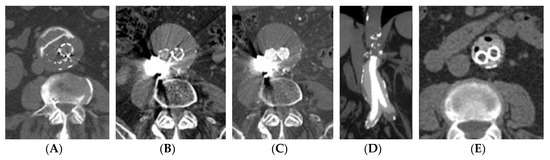

3.2. Computed Tomography (CT)—CT–Angiography (CTA)